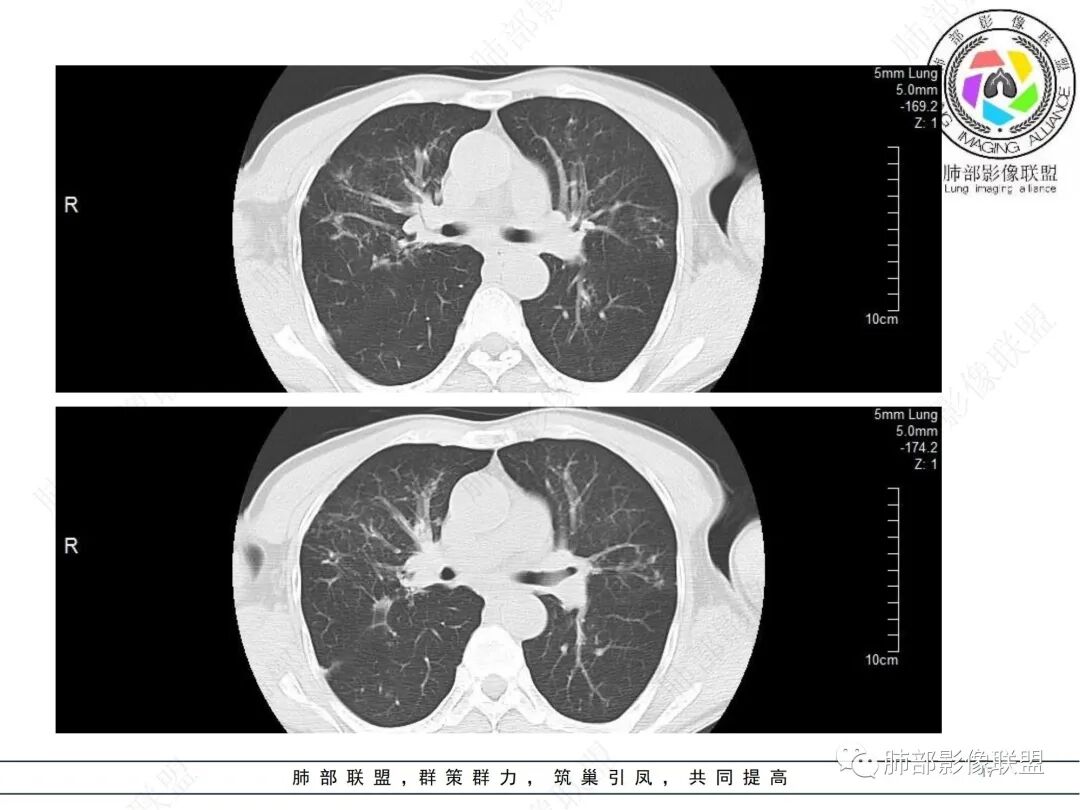

58岁男性,咳嗽胸闷3天,咳较多褐粘液痰,无发热。有2型糖尿病病史。白细胞与中性粒细胞升高。CRP升高。鳞状上皮细胞癌抗原轻度升高。结核T细胞免疫斑点实性阳性。肺炎支原体、衣原体IgG轻度升高。支气管镜显示支气管炎性改变、右肺下叶背段管腔狭窄。2.影像特点:

2022.6.24CT显示两肺弥漫性段、亚段支气管壁增厚(两肺各叶都累及),增厚的支气管壁外可见沿着支气管分布的渗出、实变影。另外远端肺内亦可见多发树芽影、结节影,其边界欠清晰。右肺下叶基底段局部胸膜下亦可见小斑片影,边界不清。2022.6.27CT显示两肺增厚的支气管壁外的渗出实变影明显增多、范围更广。远端肺内病灶亦增多、范围增大。部分位于胸膜下的病灶可见侧向融合趋势。3.病例分析:

影像学病灶双肺分布,支气管广泛增厚,较少见于普通社区肺炎,而更多见于气道侵袭性曲霉病。病原学检查证实烟曲霉感染的存在。

本案之未解之处在于三天内的进展太快,实验室炎性指标太高,合并细菌感染的可能性仍有待排除。